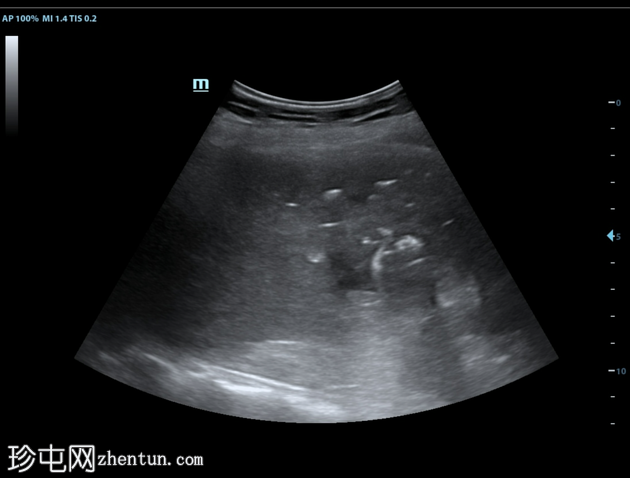

超声

纵切面(肝脏

第6和第7段)

将穿刺针插入第6段肝脓肿。抽取血脓性液体。

插入导丝,扩张通道,然后插入猪尾导管。猪尾导管用引流锁固定。导管尖端位于肝脓肿内。

对肝包膜下积液重复相同操作(未显示)。

对肝脓肿进行了经皮引流。脓液培养结果显示混合菌生长。类疽、真菌和肺结核的检测结果均为阴性。血培养未见细菌生长。

术后第3周的超声复查显示肝脓肿体积较前缩小。